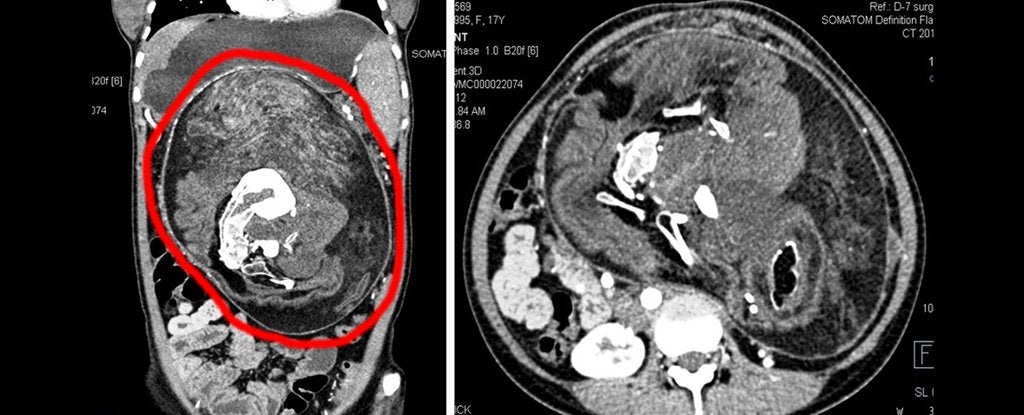

CienciaAcude a urgencias por un fuerte dolor de estómago y le encuentran los restos de su gemelo parcialmente formado

Los médicos no daban crédito a los resultados de los primeros análisis. Cuando una joven de 17 años en Patna, India, llegó a urgencias aquejada de un fuerte dolor en el estómago que había crecido hasta distorsionar su cavidad abdominal, los expertos parecían tenerlo claro: debía ser un tumor. Sin embargo, aquella masa tenía dientes.…